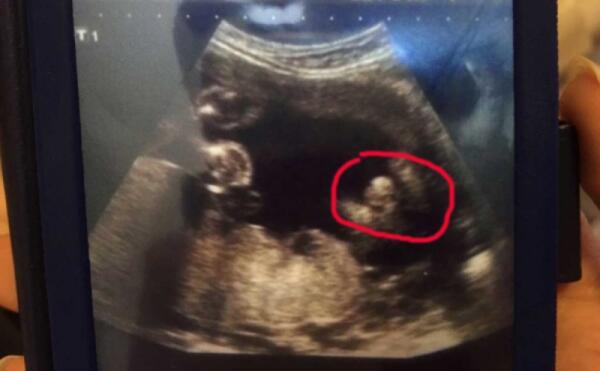

Ginecologo sbaglia la diagnosi, invece di un maschietto nasce una femminuccia